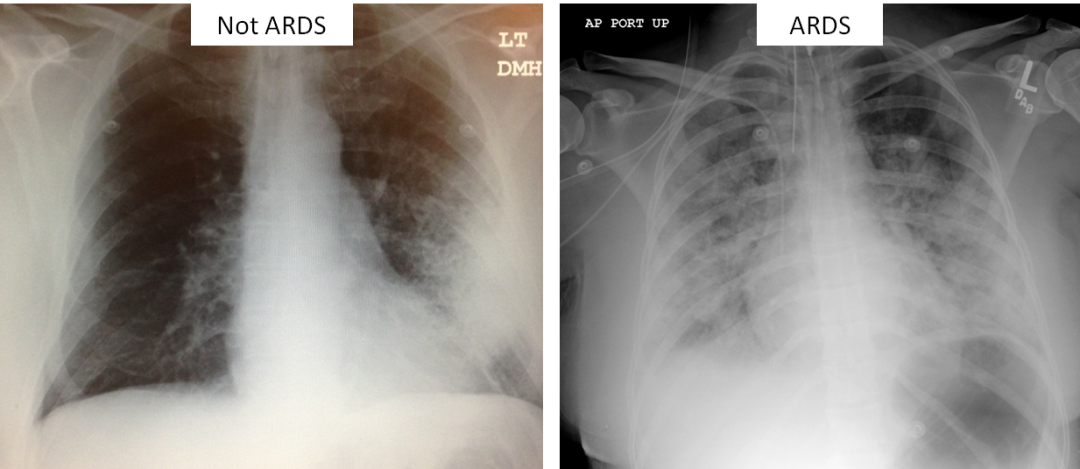

3、胸片必须有双侧模糊影

(1)轻度ARDS氧合指数

200-300

(2)中度ARDS氧合指数

100-199

(3)重度ARDS氧合指数

<100